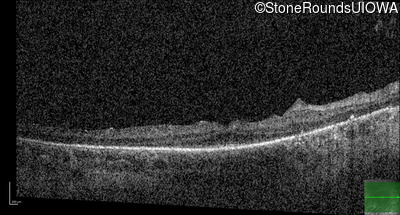

Optical Coherence Tomography - Left - 20/40

Exemplar / OCT Stack

Optical Coherence Tomography - Left - 20/50 -2